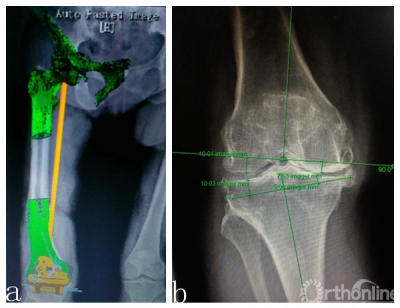

(2)畸形发生在冠状位,关节外股骨中下段;下肢全长片测量,股骨中下段内侧成角,股骨外翻角约14度(图1b);

(3)右下肢全长CT扫描,将DICOM格式文件输入Materialise Mimics17.0中,进行三维重建,确定股骨头旋转中心,膝关节中心及踝关节中心,标记股骨、胫骨机械轴,冠状位垂直于机械轴确定股骨、胫骨截骨方向,并以初次置换标准确定截骨厚度(图2a,2b);

图2 a.右下肢CT扫描,三维重建后,和右下肢全长叠加,在软件中确定股骨机械轴,并设计

截骨导板;b. 确定截骨的厚度。